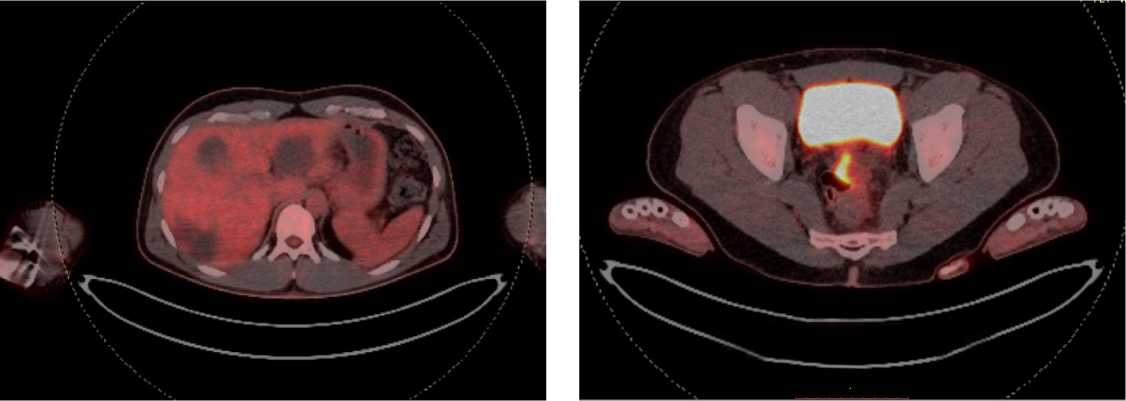

С целью оценки метаболической активности метастазов и первичной опухоли пациенту выполнено ПЭТ/КТ всего тела с 18-ФДГ: патологическая активность стенки среднеампулярного отдела прямой кишки 38,4 × 13,3 мм, SUV max 13,50 (рис. 13).

Рис. 13. Результаты позитронно-эмиссионной томографии с 18-ФДГ на фоне иммунотерапии пембролизумабом у пациента 38 лет с диагнозом метастатический колоректальный рак с признаками микросателлитной нестабильности; патологическая активность стенки среднеампулярного отдела прямой кишки 38,4 × 13,3 мм, SUV max 13,50 (март 2024 г.)

Fig. 13. Results of positron emission tomography with 18-FDG during immunotherapy with pembrolizumab in a 38-year-old patient diagnosed with metastatic MSI-H colorectal cancer; pathological activity of the wall of the mid-ampullary part of the rectum 38.4 × 13.3 mm, SUV max 13.50 (March 2024)

В настоящее время пациент продолжает получать иммунотерапию пембролизумабом, время без прогрессирования составило 18+ мес.